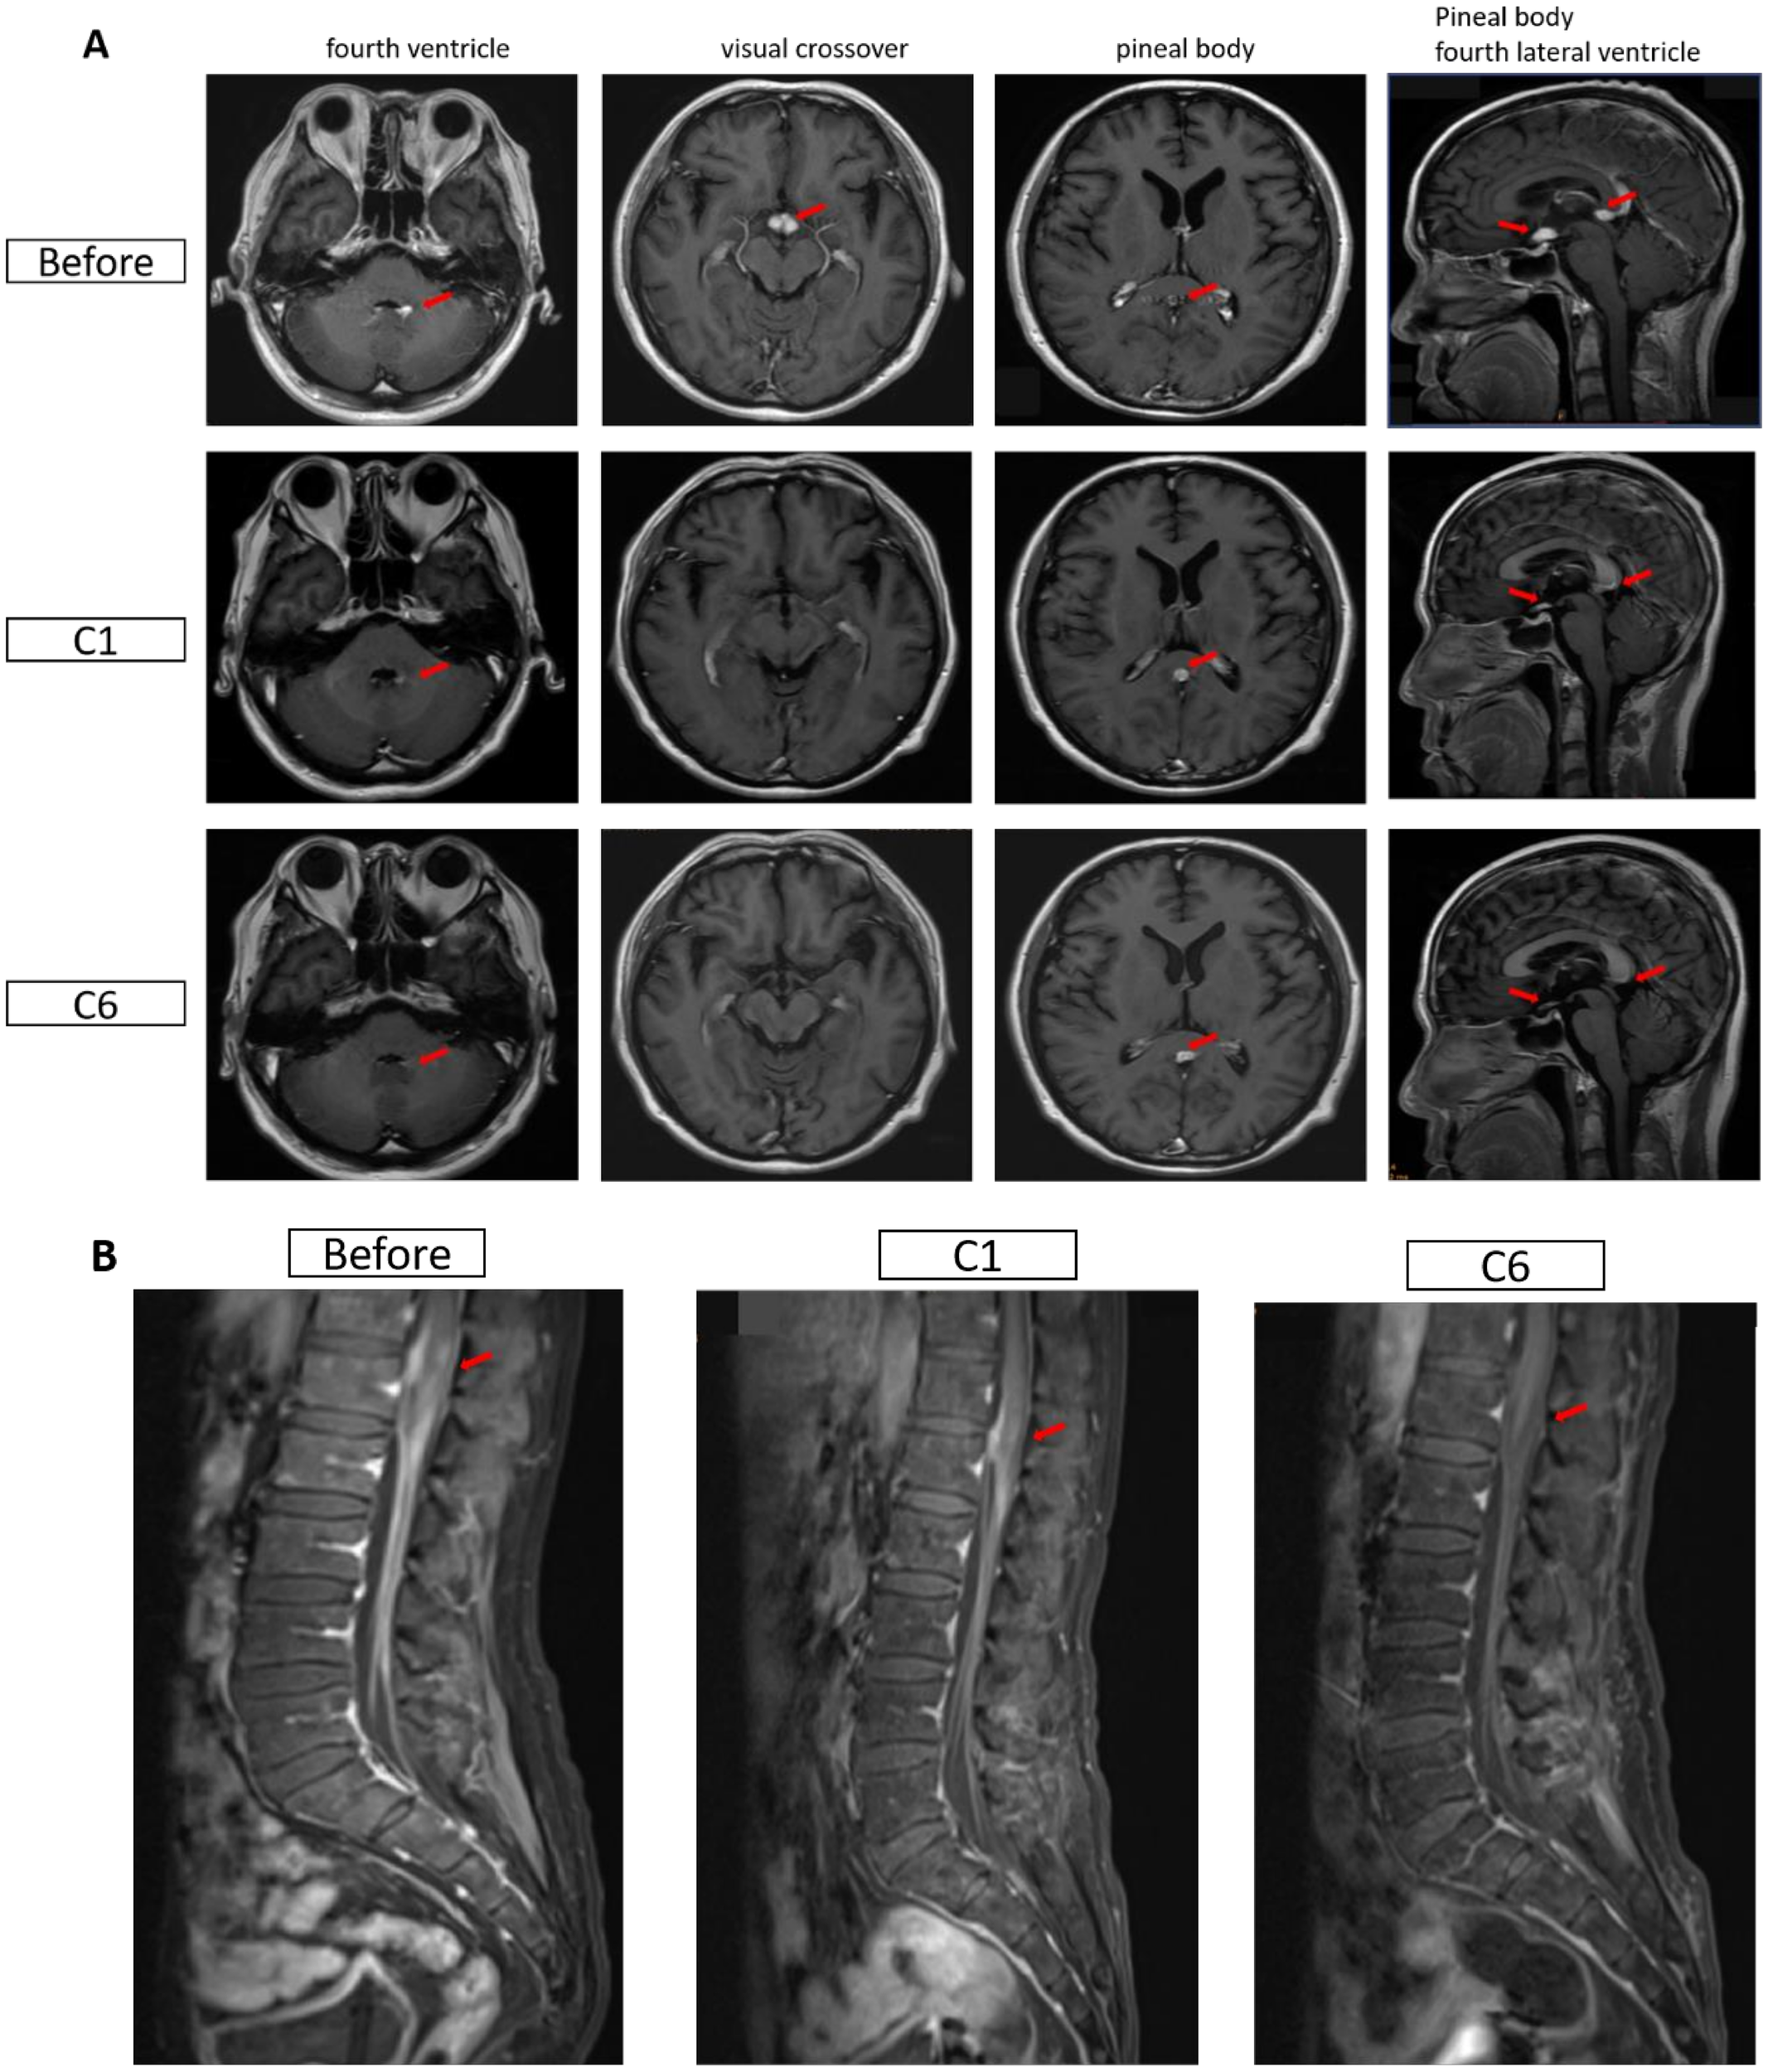

Case Report of Two Patients with Refractory HIV-Related 1 B-Cell Lymphoma Treated with the Monoclonal Antibody 2 Glofitamab for Secondary Central Nervous System 3 Involvement

You don't have a Frontiers account ? You can register here

Diffuse large B-cell lymphoma (DLBCL), the most common type of human 13 immunodeficiency virus (HIV) -related lymphoma, is associated with a high risk of 14 central nervous system (CNS) involvement. Studies have shown that CD20×CD3 15 bispecific antibodies have significant therapeutic efficacy in refractory B-cell 16 lymphoma. Preliminary reports indicate that the monoclonal antibody glofitamab can 17 penetrate the blood-brain barrier, inducing clinical responses in CNS DLBCL patients 18 by activating T lymphocytes. This report presents preliminary clinical evidence on the 19 use of glofitamab in HIV-positive patients with secondary CNS lymphoma.